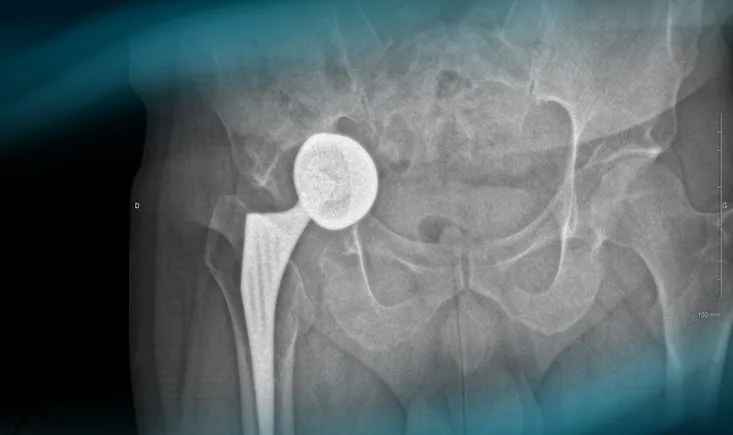

The goals of this clinical case are to discuss the different therapeutic options in case of acetabular looseni…